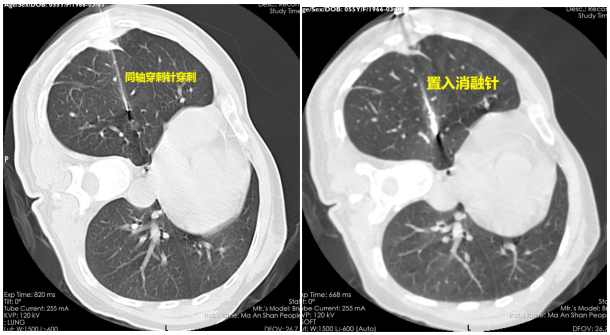

手術(shù)當(dāng)天,胸心外科手術(shù)團(tuán)隊(duì)在醫(yī)學(xué)影像科、麻醉科等科室的配合下,為李某進(jìn)行了微波消融手術(shù)。先由影像科技師進(jìn)行CT平掃,確定病灶位置及進(jìn)針的方向及深度,胸心外科醫(yī)生在李某體表定位點(diǎn)局麻后取一次性微波消融針逐層穿刺,CT再次掃描確保消融針到達(dá)準(zhǔn)確位置后用導(dǎo)線連接消融機(jī),選定恰當(dāng)功率,算好時(shí)間,開啟消融,同時(shí)術(shù)中給予心電監(jiān)護(hù)等監(jiān)測(cè),消融過(guò)程順利。消融后再次掃描CT可見(jiàn)消融范圍完全覆蓋右下肺結(jié)節(jié),手術(shù)治療成功!術(shù)后幾日復(fù)查CT,可見(jiàn)李某的肺結(jié)節(jié)變成“條索影”了,原來(lái)的結(jié)節(jié)已經(jīng)完全消失!李某后續(xù)治療定期復(fù)查即可。神奇的手術(shù)讓李某非常激動(dòng),“不開刀也可以根治腫瘤,現(xiàn)在的科技真發(fā)達(dá),以后一定讓更多的“結(jié)友們”知道這個(gè)好消息!”